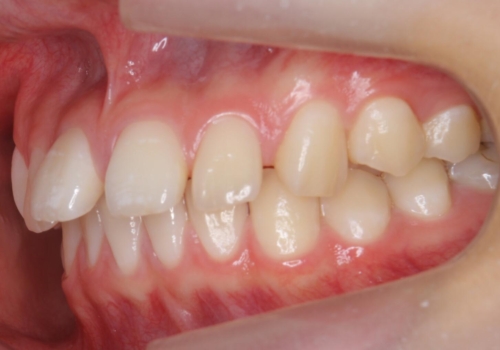

- 前歯のすき間を気にして来院。

全体矯正ではなく部分矯正で治療することになりました。

その代わり、すき間をすべて閉じるのは難しく、両脇の目立たないところに集めて治療終了しています。

低予算、短期間で治療も終了し、大変満足していただきました。

全体矯正をしていないため、就寝時にリテーナー使用は継続していただくことになっています。